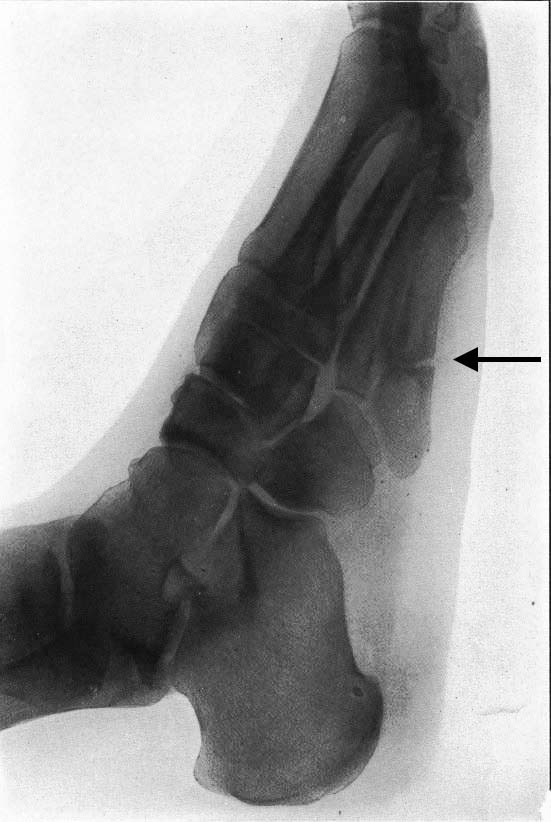

図3. 54歳男性.第5中足骨基部骨折.

【要旨】著者は,自らダンス中に躓いて受傷した.第5中足骨基部の圧痛,腫脹があり,X線写真で骨折を確認した(図3).それまでも同様の受傷機転,症状の患者を診た経験があったが臨床的に骨折と確診できないでいた.自らの骨折後,短期間に同様の症例が立て続き,いずれもX線で同一の所見を確認できた.従来,中足骨の骨折の機序は専ら直逹外力とされていたが,間接骨折であることが明らかになった.

【解説】第5中足骨基部骨折,すなわち現在でいうJones骨折(下駄履き骨折)の初報である.外科医である著者自らの受傷経験をもとに報告している点が興味深い.本文にあるように,X線以前の骨折の診断は,局所の圧痛,腫脹,皮下出血,軋音(crepitus),変形,授動変位などをもとに行なわれていた.Jonesは以前にも同様の症例を経験していたが,圧痛,腫脹以外の所見に乏しく骨折と確診できなかった.しかし,自らの骨折でX線所見による確証を得た.初期の骨X線診断は,例えばColles骨折のように既知の骨折のX線像を確認するところから始まったが,このようにX線によって初めてその存在が明らかとなった骨折も少なくなかった.6症例が供覧されており,X線写真の画質はなかなか良好であるが,少なくとも印刷でみる限り症例2,症例3以外は骨折線がはっきりしない.